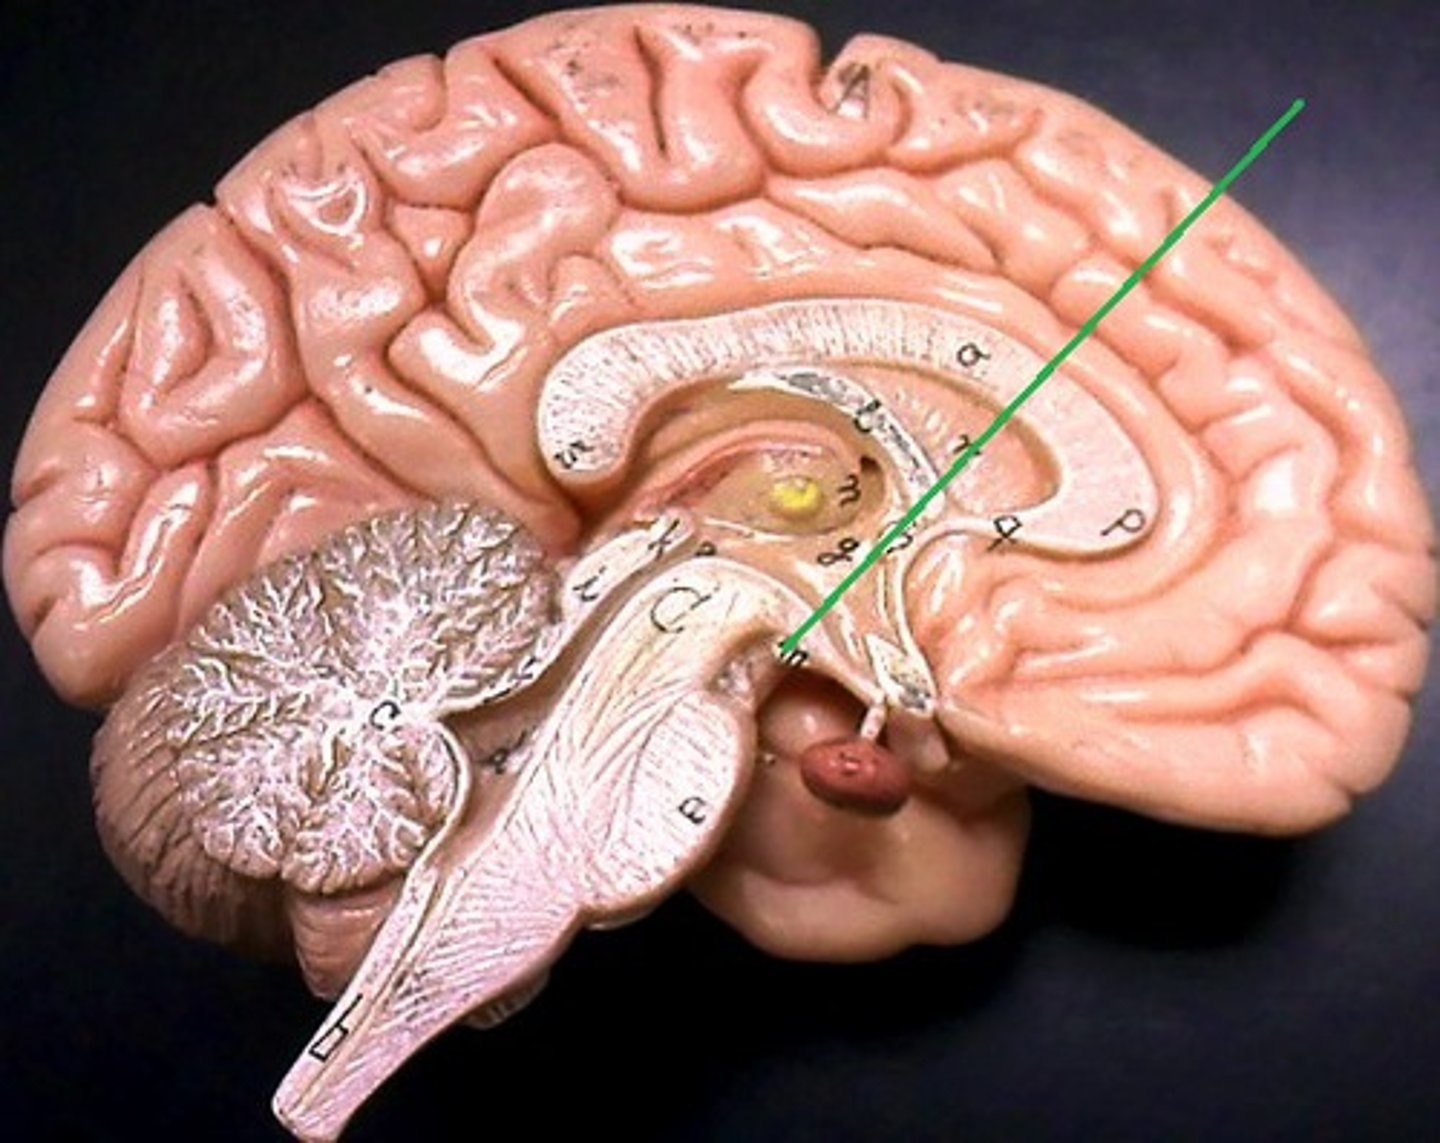

corpus callosum

septum pellucidum

fornix

right and left lateral ventricles

third ventricle